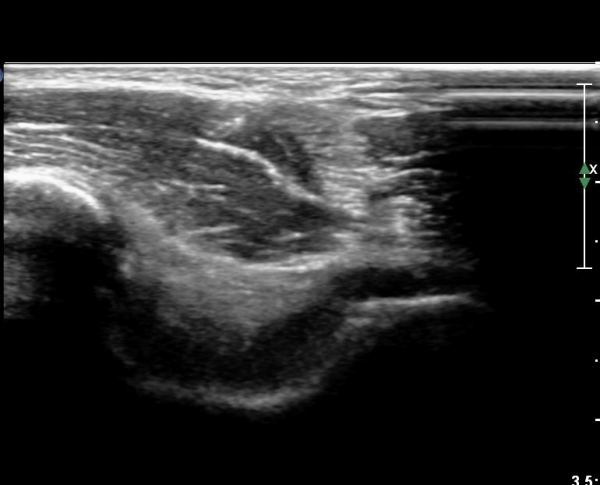

¼ÒµÎ Ⱦ´Ü¸é°Ë»ç¿¡¼­µµ ¼ÒµÎ Àü¸é¿¡ ¼ö¾×Àú·ù°¡ °üÂûµÊ(»çÁø 5).

Áֵοͳ» ÁÖ»çÄ¡·á¸¦ À§ÇØ È¯ÀÚ¸¦ ¿·À¸·Î ´¯°ÔÇÏ°í ÆÈ²ÞÄ¡¸¦ Æí »óÅ¿¡¼­ ¸ö ¿·¿¡ ÆÈÀ» ´ë°í ŽÃËÀÚ¸¦

ÁֵοͿ¡ ȾÀ¸·Î ´í »óÅ¿¡¼­ ¼ö¾×Àú·ù°¡ °¡Àå Àß º¸ÀÌ°í ¼ö¾× Àú·ù¿¡ Áֻ簡 °¡´ÉÇÑ À§Ä¡¿¡¼­

¼ö¾×Àú·ù¸¦ È®ÀÎÇÑ´Ù(»çÁø 6)